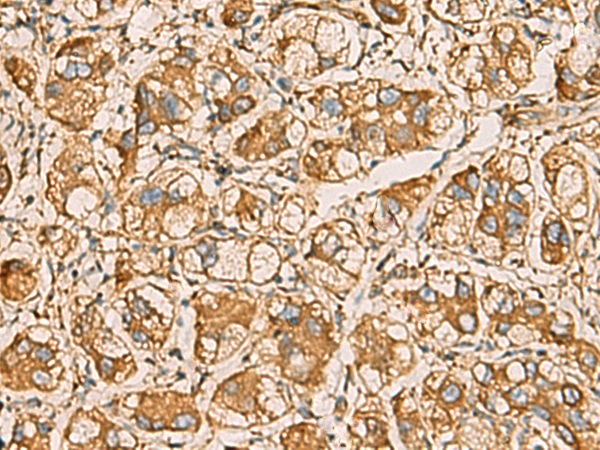

IHC positive control: |

Human liver cancer and Human prostate cancer |

IHC Recommend dilution: |

50-200 |